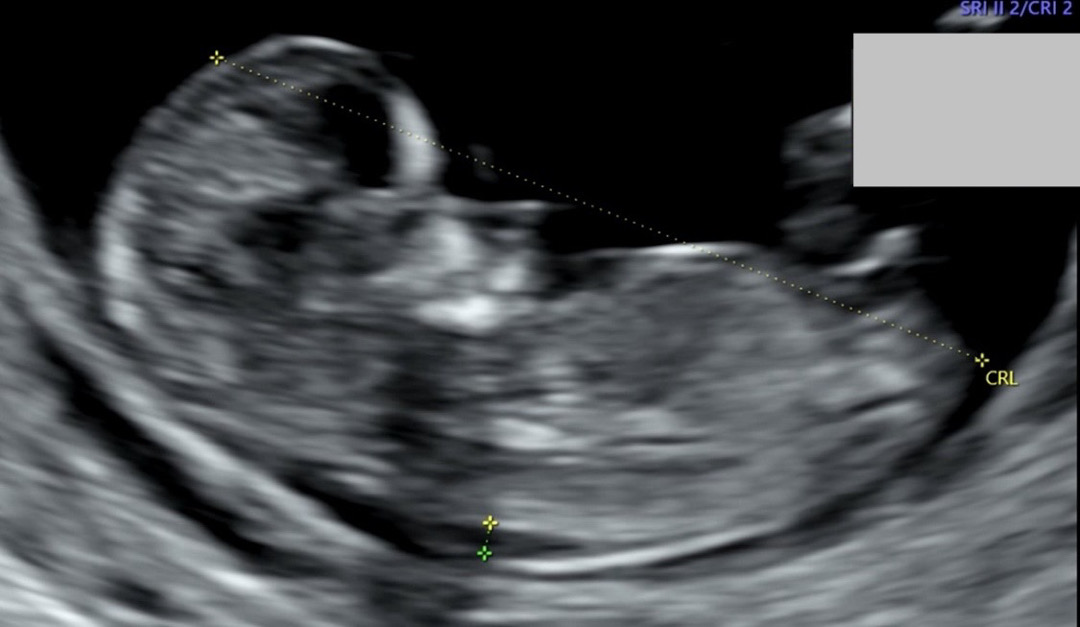

/ 성별질문

각도법봐주세요!!🥹

초음파보고왔는데 제 추측으로는 잘모르겠어요. 고수님들 도와주세요🥺

2026년 4월 베동